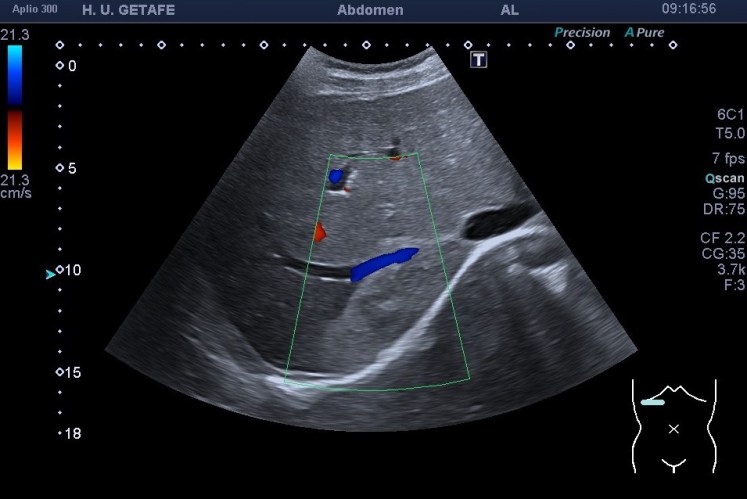

El caso en si mismo no tiene gran relevancia a no ser que la sospecha fuese que la masa que sabemos que es de un hemangioma atípico fuera de otra índole, pero ¿cómo podríamos sospechar que una LOE es maligna? Bien, hay varias maneras, hoy te quiero explicar una que estas imágenes cuentan muy bien. Cuando una lesión ocupante de espacio o LOE es de sospecha maligna, se puede reconocer por la relación que mantiene con los vasos de la región que está ocupando. En este caso puedes ver perfectamente que la LOE está coexistiendo perfectamente con la rama de la suprahepática a la que está envolviendo, abrazando, pero sin desplazarla, sin agredirla, sin infiltrarla, es decir, la está respetando. Le permite el normal flujo de la sangre a través de ella (imagen 3), no la ocluye ni la tapona y la pared del vaso está respetada. Por tanto, esta lesión que por su tamaño y aspecto podría ser sospechosa (imagen 4 y 5), se torna amable al ver que respeta al vaso que toca.

Podemos concluir, de modo general, que aquellas LOES que no respeten los vasos locoregionales en el modo antes mencionado, pueden aumentar el grado de sospecha de malignidad para el radiólogo, por eso es muy importante que estemos siempre muy atentos a estas relaciones anatómicas y las documentemos siempre muy detalladamente.